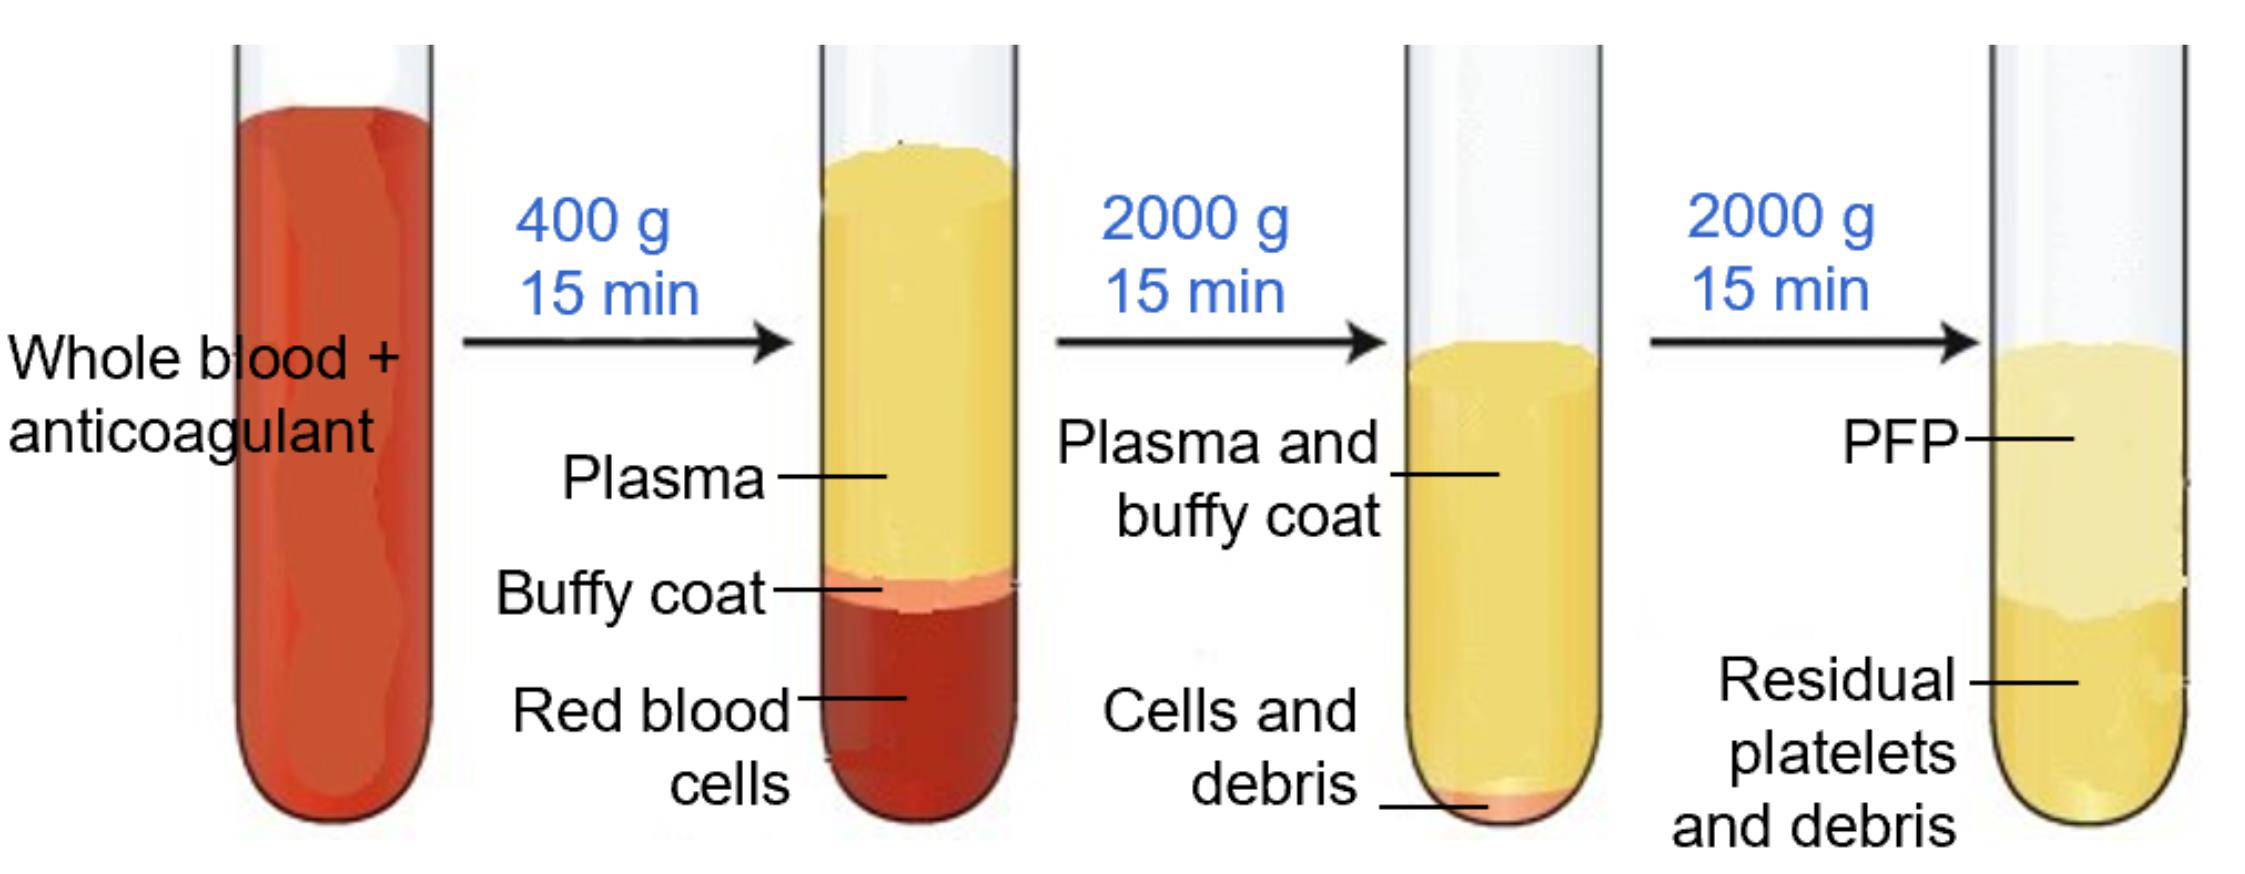

C. Preparation of platelet-free plasma (PFP) (timing: 45 min)

Note: This section describes the procedure for platelet-free plasma (PFP) preparation for isolation of EVs from the whole blood sample.

1. Centrifuge EDTA blood (2 mL) at 400× g for 15 min at room temperature.

2. Transfer supernatant carefully to the plastic round-bottom tube, leaving ~500 μL above the buffy coat so that the red cell pellet and the buffy coat with platelets and white cells are discarded.

3. Centrifuge at 2,000× g for 15 min at room temperature.

4. Transfer supernatant, leaving ~100 μL behind.

5. Perform a final centrifugation at 2,000× g for 15 min.

6. Aliquot the supernatant, leaving ~100 μL behind. EVs are now concentrated in the supernatant, which will be used for analysis. This supernatant is devoid of platelets and hence known as PFP [14].

Critical: The first centrifugation step at a lower speed (typically, 400× g) is performed to remove intact cells and large debris while preventing excessive mechanical stress that could lead to cell lysis and artificial EV release. If a higher speed were used initially, fragile cells, especially platelets, could rupture, artificially increasing EV counts and altering their composition. This low-speed centrifugation effectively separates whole cells from the plasma, ensuring that only naturally circulating EVs remain for subsequent isolation and analysis (Troubleshooting 1).

Note: At each step, new micropipette tips should be used to avoid contamination of cells in the PFP (Figure 1). Care should be taken when removing tubes from the centrifuge, as the layers are easily disturbed; unlike standard cell pellets, EV fractions do not form solid pellets and remain loosely associated with the supernatant (Troubleshooting 2).

Figure 1. Platelet-free plasma (PFP) separation. PFP is the upper 100–200 μL layer, which is devoid of platelets, cell debris, and buffy coat.